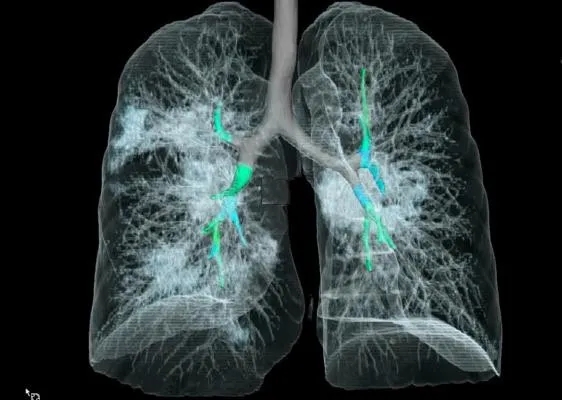

采用CT三维成像技术,

暴露在人们裸眼眼前,

到处是斑片状磨玻璃影(见下图)。

01-4.webp

图片来自Radiology